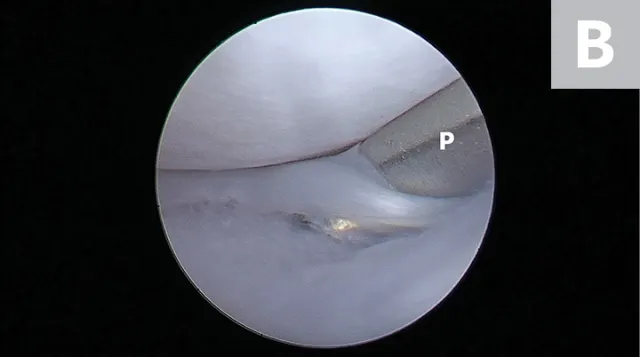

FIGURE 4A

Arthroscopic images showing a small bucket handle tear in the caudal pole of the medial meniscus (A; arrowheads). The meniscus is palpated with a meniscal probe (B; P). The torn portion of meniscus is removed with an arthroscopic shaver (C; S). After removal of the diseased meniscus, the remaining outer rim of the meniscus is left intact (D).